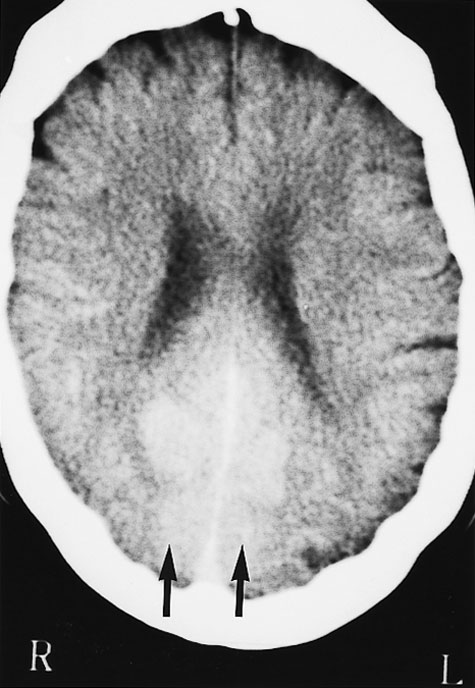

Computed tomography (CT) brain scan was performed three hours after the completion of coronary angiography. No additional contrast was used. The CT brain scan (Box 1) showed marked bilateral contrast enhancement of the occipital lobes and no evidence of a cerebral haemorrhage. Intravenous heparin treatment was commenced. By the following day, she was able to see shapes and shadows but had persistent headache and nausea. A repeat CT brain scan did not show any residual abnormality. During the next 48 hours, her vision progressively returned. She described flashing lights in her right eye and had evidence of right homonymous hemianopia. Magnetic resonance imaging (MRI) showed increased signals in the grey matter of the medial aspect of the left occipital lobe, on a background of longstanding mild ischaemic changes consistent with her age and cardiac risk factors (Box 2A). Magnetic resonance angiography (MRA) showed patency of both posterior cerebral arteries, with dilatation of branches supplying the left occipital lobe (Box 2B). Heparin therapy was ceased, as there was no evidence of acute thromboembolism or acute infarction. She fully regained her vision five days after coronary angiography.

These mechanisms seem possible in our patient, and they were supported by the results of imaging studies. There were bilateral occipital lobe changes when she had clinical cortical blindness (Box 1), representing oedema and passage of contrast across the blood–brain barrier. Cortical blindness is synonymous with bilateral homonymous hemianopia from involvement of the occipital cortex.1 When our patient was recovering and exhibiting right homonymous hemianopia, there were MRI changes in the left occipital gyrus, and differences in the calibre of the vessels on the two sides (Box 2).

1: Computed tomography scan of the patient's brain three hours after completion of coronary angiography, when she had cortical blindness

No additional contrast was given. There is marked bilateral contrast enhancement of the medial aspect of both occipital lobes in a symmetric distribution (arrows).